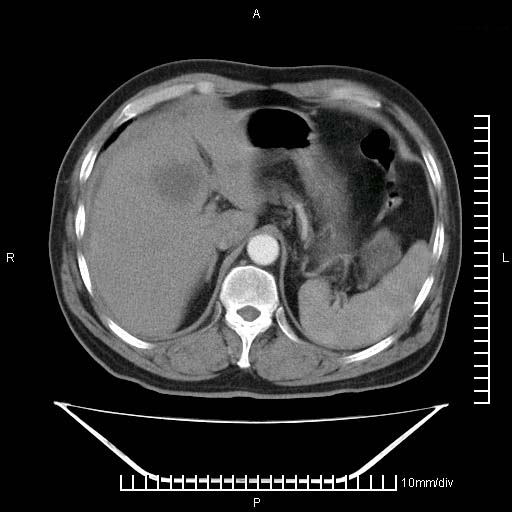

标题: CT25082:肝脏增强:男性,70岁 [打印本页]

标题: CT25082:肝脏增强:男性,70岁

患者以心脏疾病收住院,腹部无明显症状,b超查肝脏有占位。

增强效果不理想。考虑转移,胆囊壁明显增厚,不排除胆囊癌肝转移。

病灶无强化,考虑囊肿。

牛眼征,中心坏死无强化,外缘强化,最外缘又见低密度,考虑转移,与脓肿鉴别

肝内多发转移瘤,右下肺炎症并少量胸水。胃壁增厚建议胃镜,胰尾部“病变”为肠管。

1)肝脏多发性转移瘤(不排除胰尾癌转移所致可能)。2)腹水。3)右侧少量胸腔积液。

ct25082 结果:转移瘤

外院mr结果:胰尾恶性占位。

肝多发低密度灶;轻度强化,较水密度高,考虑转移,不排除肝脓肿